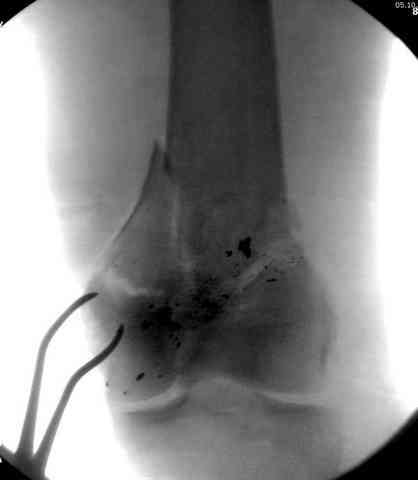

2 внутрисуставной перелом дистального бедра с удалением пули

Условием для обязательного удаления пули считаем ее внутрисуставное расположение из-за возможного сатурнизма, или когда во время операции она без труда удаляется, а также поверхностно расположена.

Компартамент-синдром -при огнестрельных переломах наблюдался очень редко, хотя рутинно проводился мониторинг на КС. Наши КС в большинстве были после переломов тибиал плато и после повреждения сосудов от огнестрельного оружия.

После восстановления сосудов проводили профилактику компартамент-синдрома фасциотомией, которая благоприятно действовала на проходимость, и сосуд не закупоривался вторично тромбом.